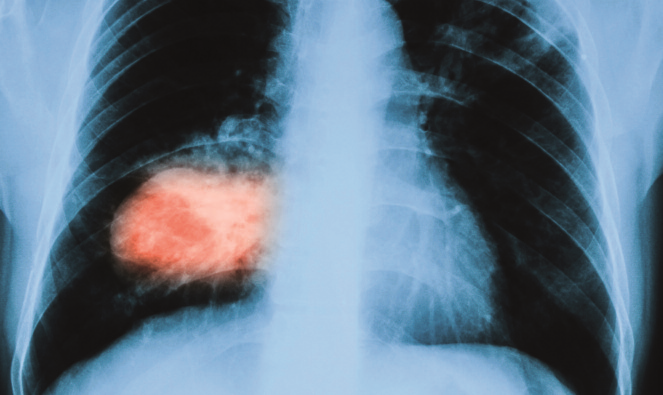

Questo articolo prende spunto da alcune affermazioni che sono state fatte in occasione del forum di “Toscana Medica” n. 6 del giugno 2017 “Adenocarcinoma polmonare: nuove strategie terapeutiche” in merito alla diagnosi precoce del tumore del polmone.

Riguardo al primo aspetto occorre tenere presente che nello studio National Lung Screening Trial (NLST), eseguito negli USA nei primi anni 2000 su più di 50.000 soggetti a rischio, lo screening del tumore polmonare con Tc a basso dosaggio (LDCT) ha ridotto del 20% la mortalità per cancro del polmone in modo statisticamente significativo. Di conseguenza dopo la pubblicazione dei risultati nel 2011 in USA le linee guida per lo screening del tumore polmonare sono state rapidamente aggiornate dalle principali agenzie tra cui la governativa USPSTF, così che la LDCT è, allo stato attuale, raccomandata in questo Paese per i soggetti ad alto rischio secondo un definito protocollo. Recentemente si sono allineate alle linee guida statunitensi anche quelle canadesi. In Canada, che come noto ha un servizio sanitario pubblico di tipo europeo, a breve inizierà infatti un programma nazionale di screen-ing con LDCT.

Nel 2011 in un Documento di Consenso chiamato Pisa Statement, ripreso in un documento di indirizzo dell’Osservatorio Nazionale Screening, i responsabili degli studi randomizzati europei, tra cui ITALUNG realizzato in Regione Toscana, hanno deciso di continuare la valutazione dei risultati. Oggi siamo in attesa (nel 2018) che il più grosso trial europeo (NELSON, in corso in Olanda), eseguito su più di 15.000 soggetti, produca i suoi risultati che si aggiungeranno a quelli di altri studi più piccoli già pubblicati. Su questa base si sta avviando a livello europeo un processo di valutazione di qualità (HTA) con la promozione di studi pilota nei diversi paesi. Nella Regione Toscana lo studio randomizzato ITALUNG, interamente finanziato dalla Regione con finalità di valutazione evidence-based nell’ambito della collaborazione internazionale ed europea, è stato condotto proprio per verificare l’uso di questa tecnologia evitando la sua diffusione senza valutazione ed è stato eseguito su circa 3.000 soggetti a rischio. I risultati recentemente pubblicati su BMJ-Thorax (2017) si allineano con quelli avuti negli USA con una riduzione di mortalità per cancro del polmone del 30% nel braccio che è stato sottoposto a LDCT, rispetto al braccio di controllo. Pur nella ridotta rappresentatività statistica del campione studiato, i risultati concorrono all’evidenza che si sta costruendo in Europa, nella direzione di continuare una cauta, indipendente, politica di valutazione di tecnologia (HTA). Oltre infatti all’evidenza sui benefici per cui sarà fondamentale il contributo nei prossimi mesi dei dati olandesi, esistono alcuni problemi ancora aperti, di cui i principali sono il numero di falsi positivi (non sembra rilevante, invece, quello dei falsi negativi anche perché nessun studio ha finora prospettato una problematica legata ai falsi negativi alla Tc) e la selezione di soggetti ad alto rischio. Per quanto riguarda il problema dei falsi positivi, anche se il termine falsi positivi dovrebbe essere riservato ai soli rari casi in cui si procede inutilmente ad un accertamento invasivo come la biopsia (0,1-4% nei vari studi) o addirittura all’intervento chirurgico (0,1-1,1%), rimane comunque la problematica del dovere ripetere, in una percentuale di casi, controlli di follow-up per potere arrivare ad una definizione diagnostica. Tuttavia, la stessa definizione di “falso positivo” deve oggi essere ridiscussa e valutata alla luce dei risultati della lettura volumetrica proposta dagli olandesi e da altri studi. In ogni caso l’expertise del centro di screening è il miglior antidoto per questo tipo di problematica.

Inoltre va considerato che si sta sempre più affermando la convinzione che lo screening polmonare debba essere riservato a soggetti particolarmente selezionati, individuati non solo per il loro rischio di fumo, ma anche per altri fattori di rischio (per esempio familiarità, rischio professionale, rischio ambientale ecc.) e per la positività a biomarcatori oncologici (di cui ITALUNG ha pubblicato recentemente risultati estremamente promettenti sull’International Journal of Cancer, con i risultati dell’ITALUNG BIOMARKER PANEL). Fra i soggetti da screenare, un’attenzione particolare va sicuramente riservata agli esposti ad amianto per i quali, in base al profilo di rischio di esposizione ed agli altri criteri di eleggibilità come età e fumo, è indicata l’offerta di un efficace test di diagnosi precoce come la LDCT.